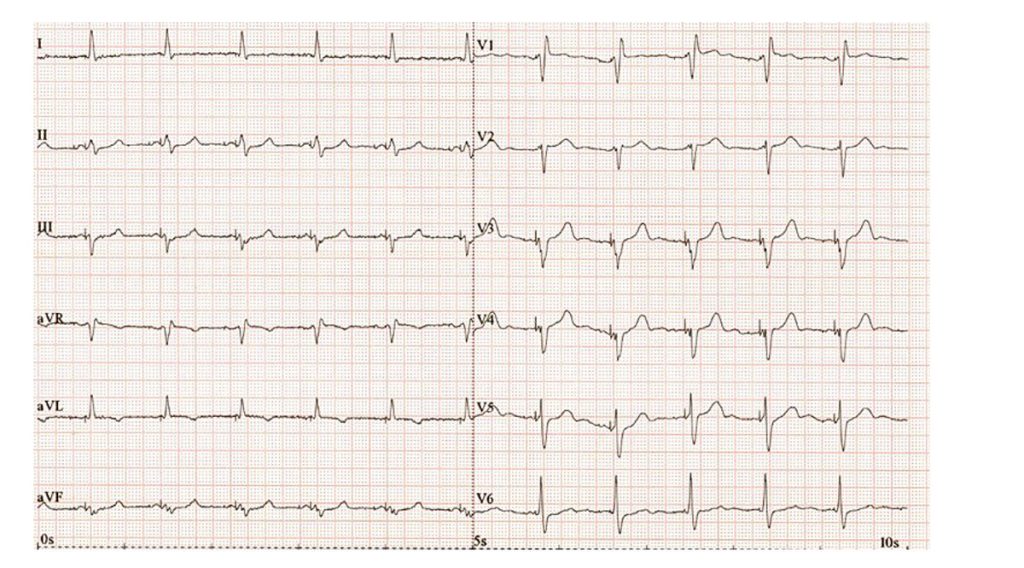

Obr. 3 EKG u pacienta se zhoršením srdečního selhání

Elektrokardiografie prokázala fibrilaci síní. Na obrázku je patrná komorová stimulace bez zřetelné pravidelné aktivity síní, se vzhledem blokády pravého Tawarova raménka a širokým QRS komplexem, četné komorové extrasystoly (obr. 3).